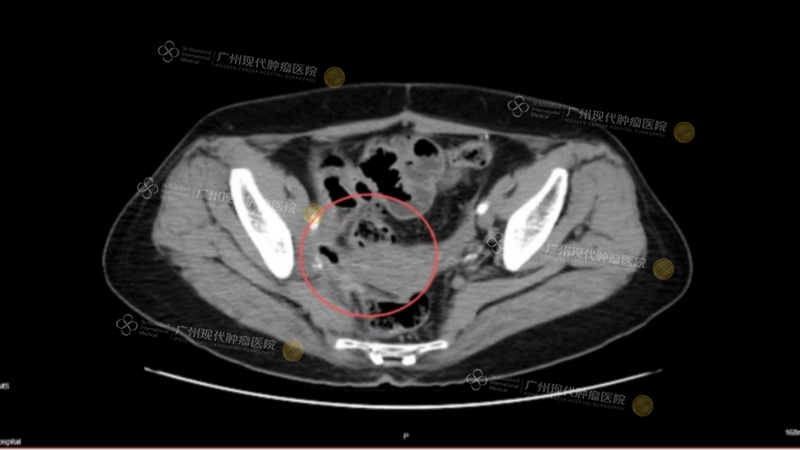

黄作平教授曾参与治疗一位卵巢癌Ⅳ期患者,入院时患者已出现腹腔广泛转移,侵犯肠管,经多线治疗后效果不佳。黄作平团队为其进行基因检测,发现可靶向突变位点,并经过MDT会诊后,治疗策略由此确定:西医采用介入化疗联合靶向治疗,同时配合中医调理改善体质。经治疗后,该患者肿瘤标志物下降,影像学显示肿瘤明显缩小;患者体力恢复,能够正常进食,生活质量大幅提升。

(治疗前CT)